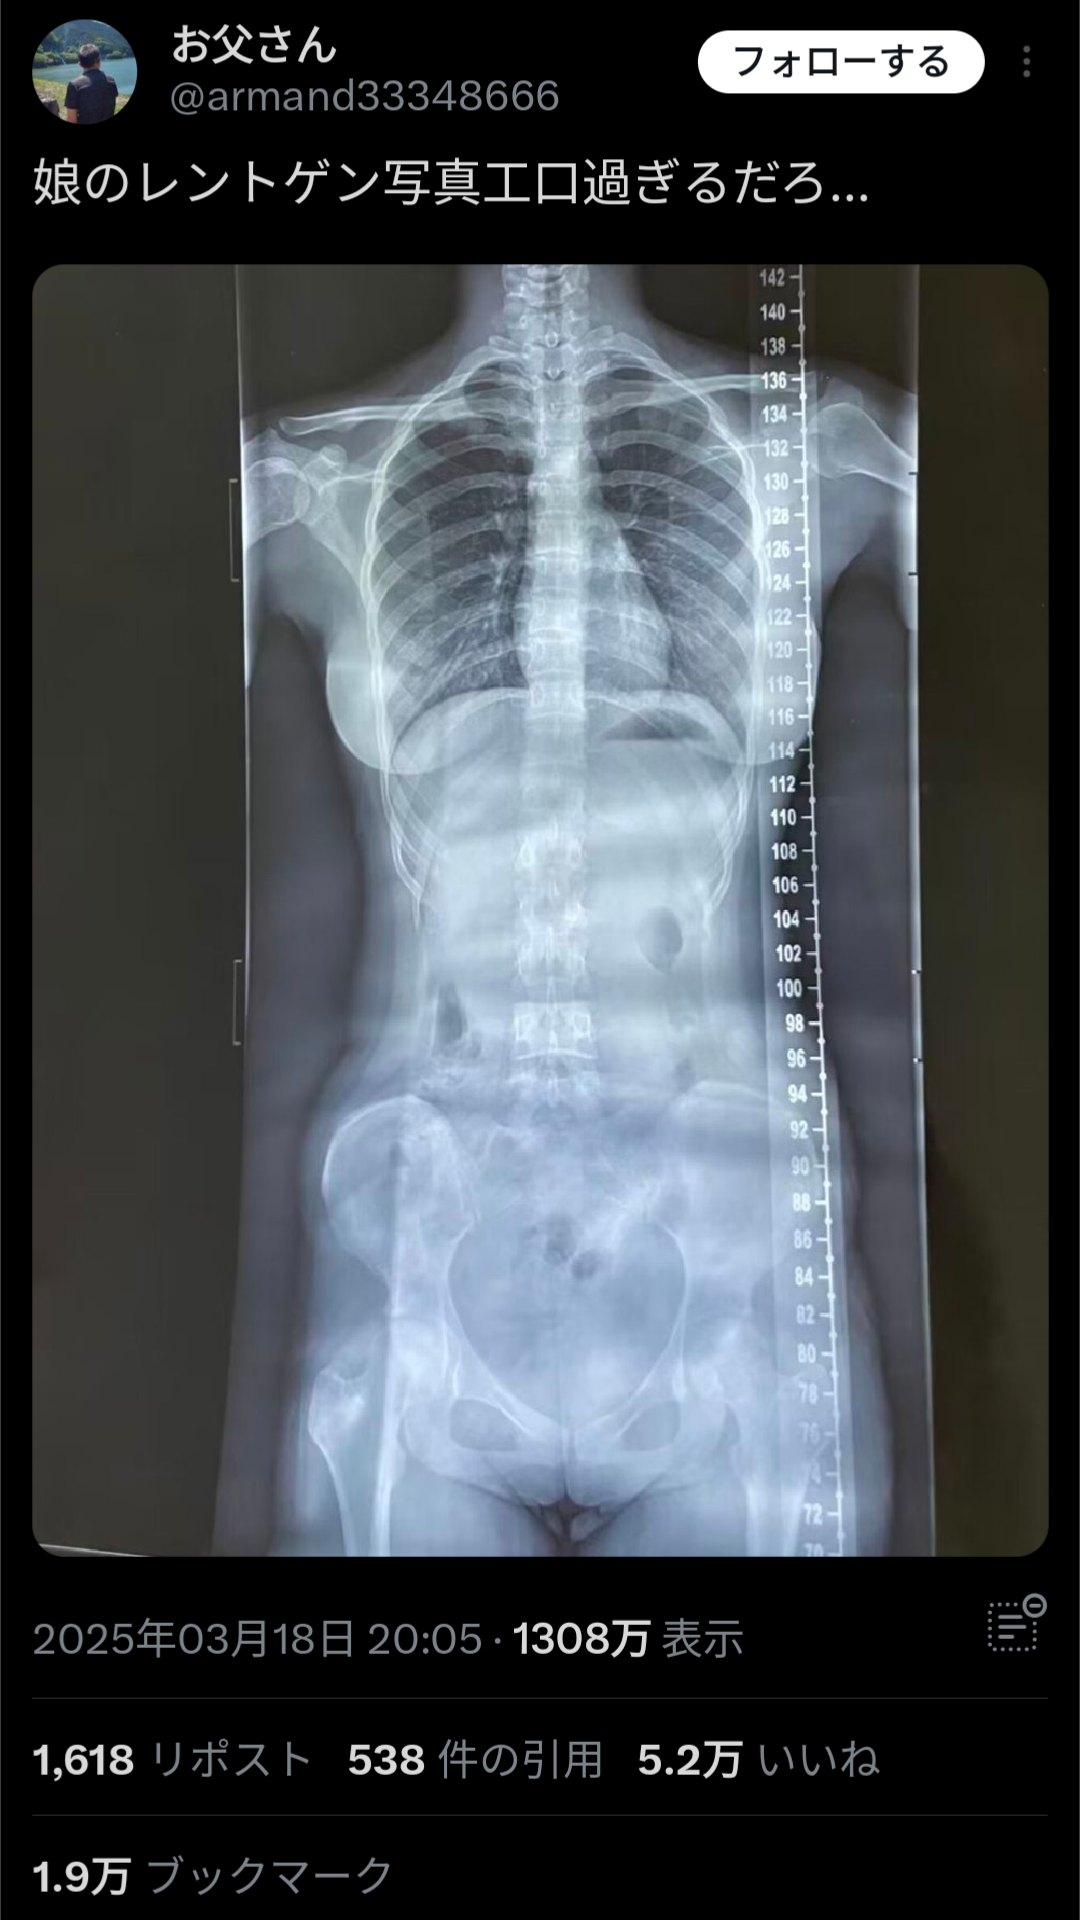

トータル:451HIT